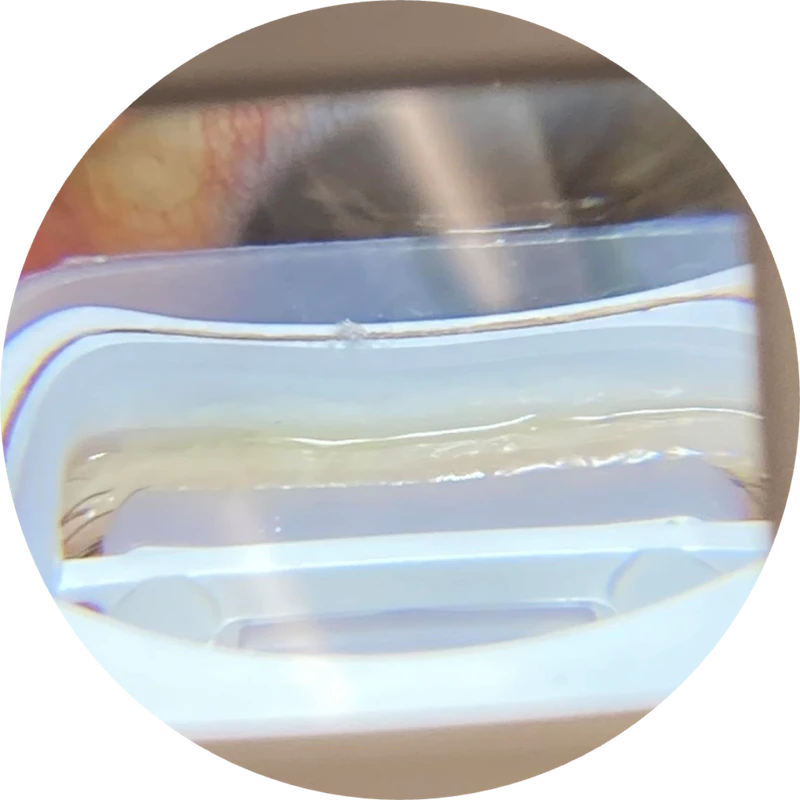

Discover the remarkable LashCam® — a revolutionary WiFi camera designed to provide a close-up view of your eyelid margins like never before. With its high-resolution 80X magnification capability, LashCam® instantly captures detailed images that reveal the presence of bacterial biofilm, debris, and scurf. During your examination, your doctor will guide you to use an iOS or Android device, allowing you to witness firsthand what they see through the slit lamp. This experience helps patients understand underlying causes of inflammation and dry eye symptoms, making it easier to recognize the importance of BlephEx® treatment.